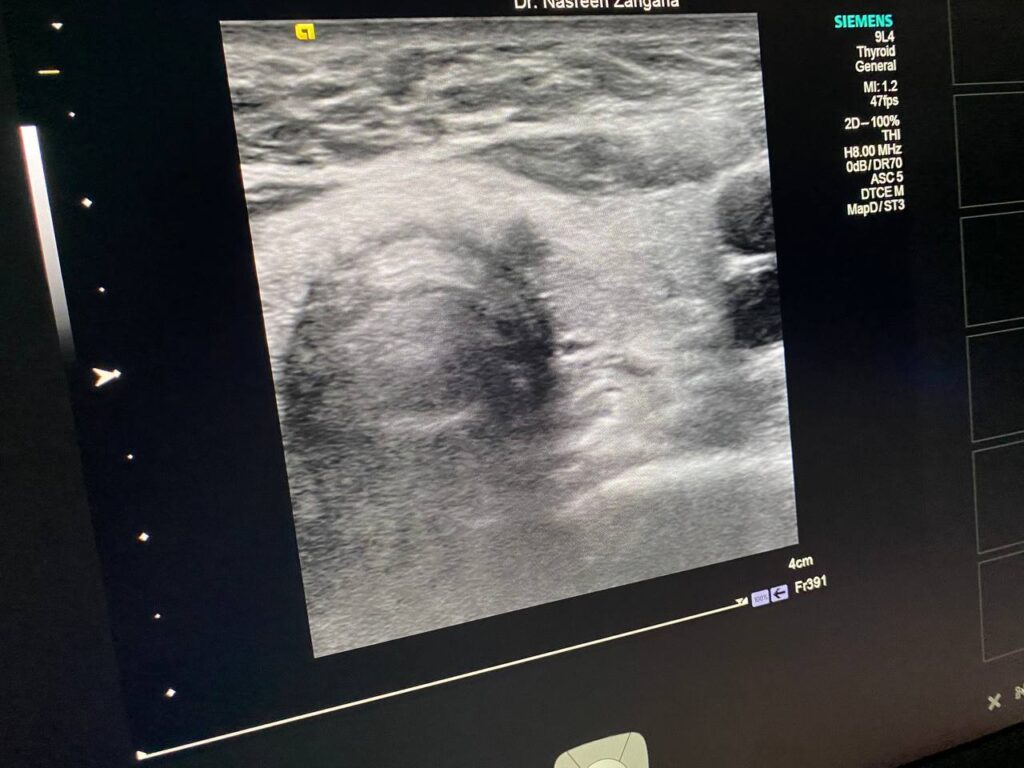

in the left sided of the isthmus presence of two hypoechoic masses , size 3.2×3.3mm, it has indistinct margin , suspicious nodule can not be exclude for further study , the other mass 3.6×2.4mm more regular , mostly lymph node , please for further study TIRADS U4